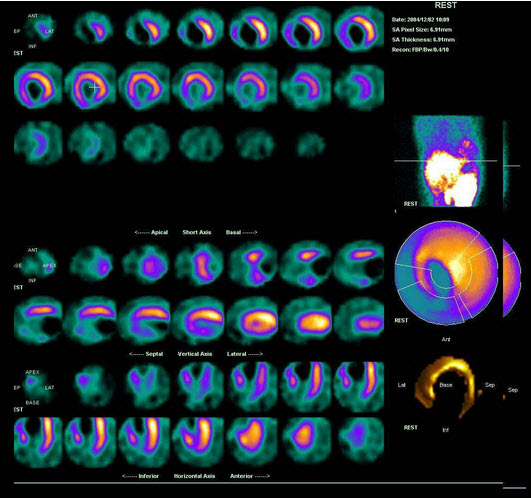

55、多项选择题

男性,65岁,急性心前区疼痛2天入院。行静息Tc-MIBI心肌显像如图,可能的诊断是()

A.下后壁心肌梗死

B.心尖心肌梗死

C.间壁严重缺血

D.梗死区无存活心肌

E.部分前壁心梗

男,49岁,反复发作心前区疼痛半年,行负荷、静息F-FDG心肌代谢显像如图,诊断是()

A.未见心肌缺血表现

B.心尖心梗

C.心尖、前间壁、部分下壁缺血

D.心尖室壁瘤形成

E.以上都不是